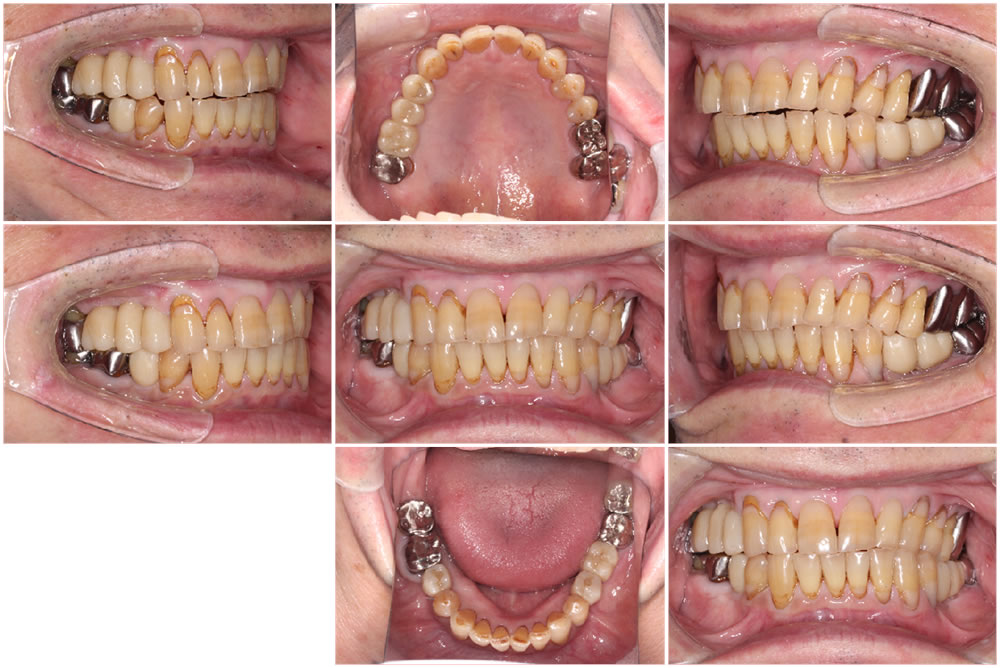

初診時の口腔内

こちらの患者さまは、右上奥歯の欠損を治療しいとのことで来院されました。右上欠損部は、インプラントを埋入するために必要な骨量が不足していたため、サイナスリフトという骨造成法を併用し、インプラント手術を実施する計画を立てました。

治癒期間を経て、ジルコニアで製作した上部構造を装着、最終的な咬み合わせを調整して治療完了です。